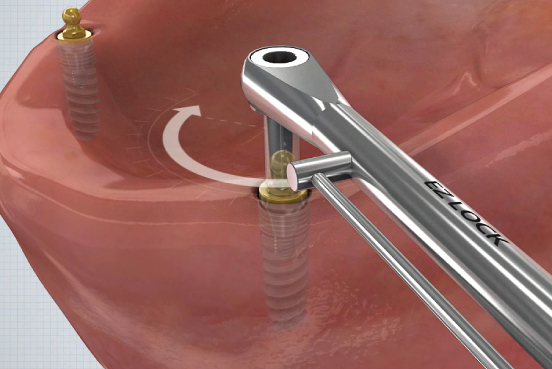

③

- Fixture의 식립방향에 따라 Housing Positioner를 선택▼

④

- H/P를 끼우고 좌우로 움직이면서 교합면과 평행하게 Housing 장착▼

⑤

- 장착이 완료되면 손잡이 부분을 시저로 잘라냄▼